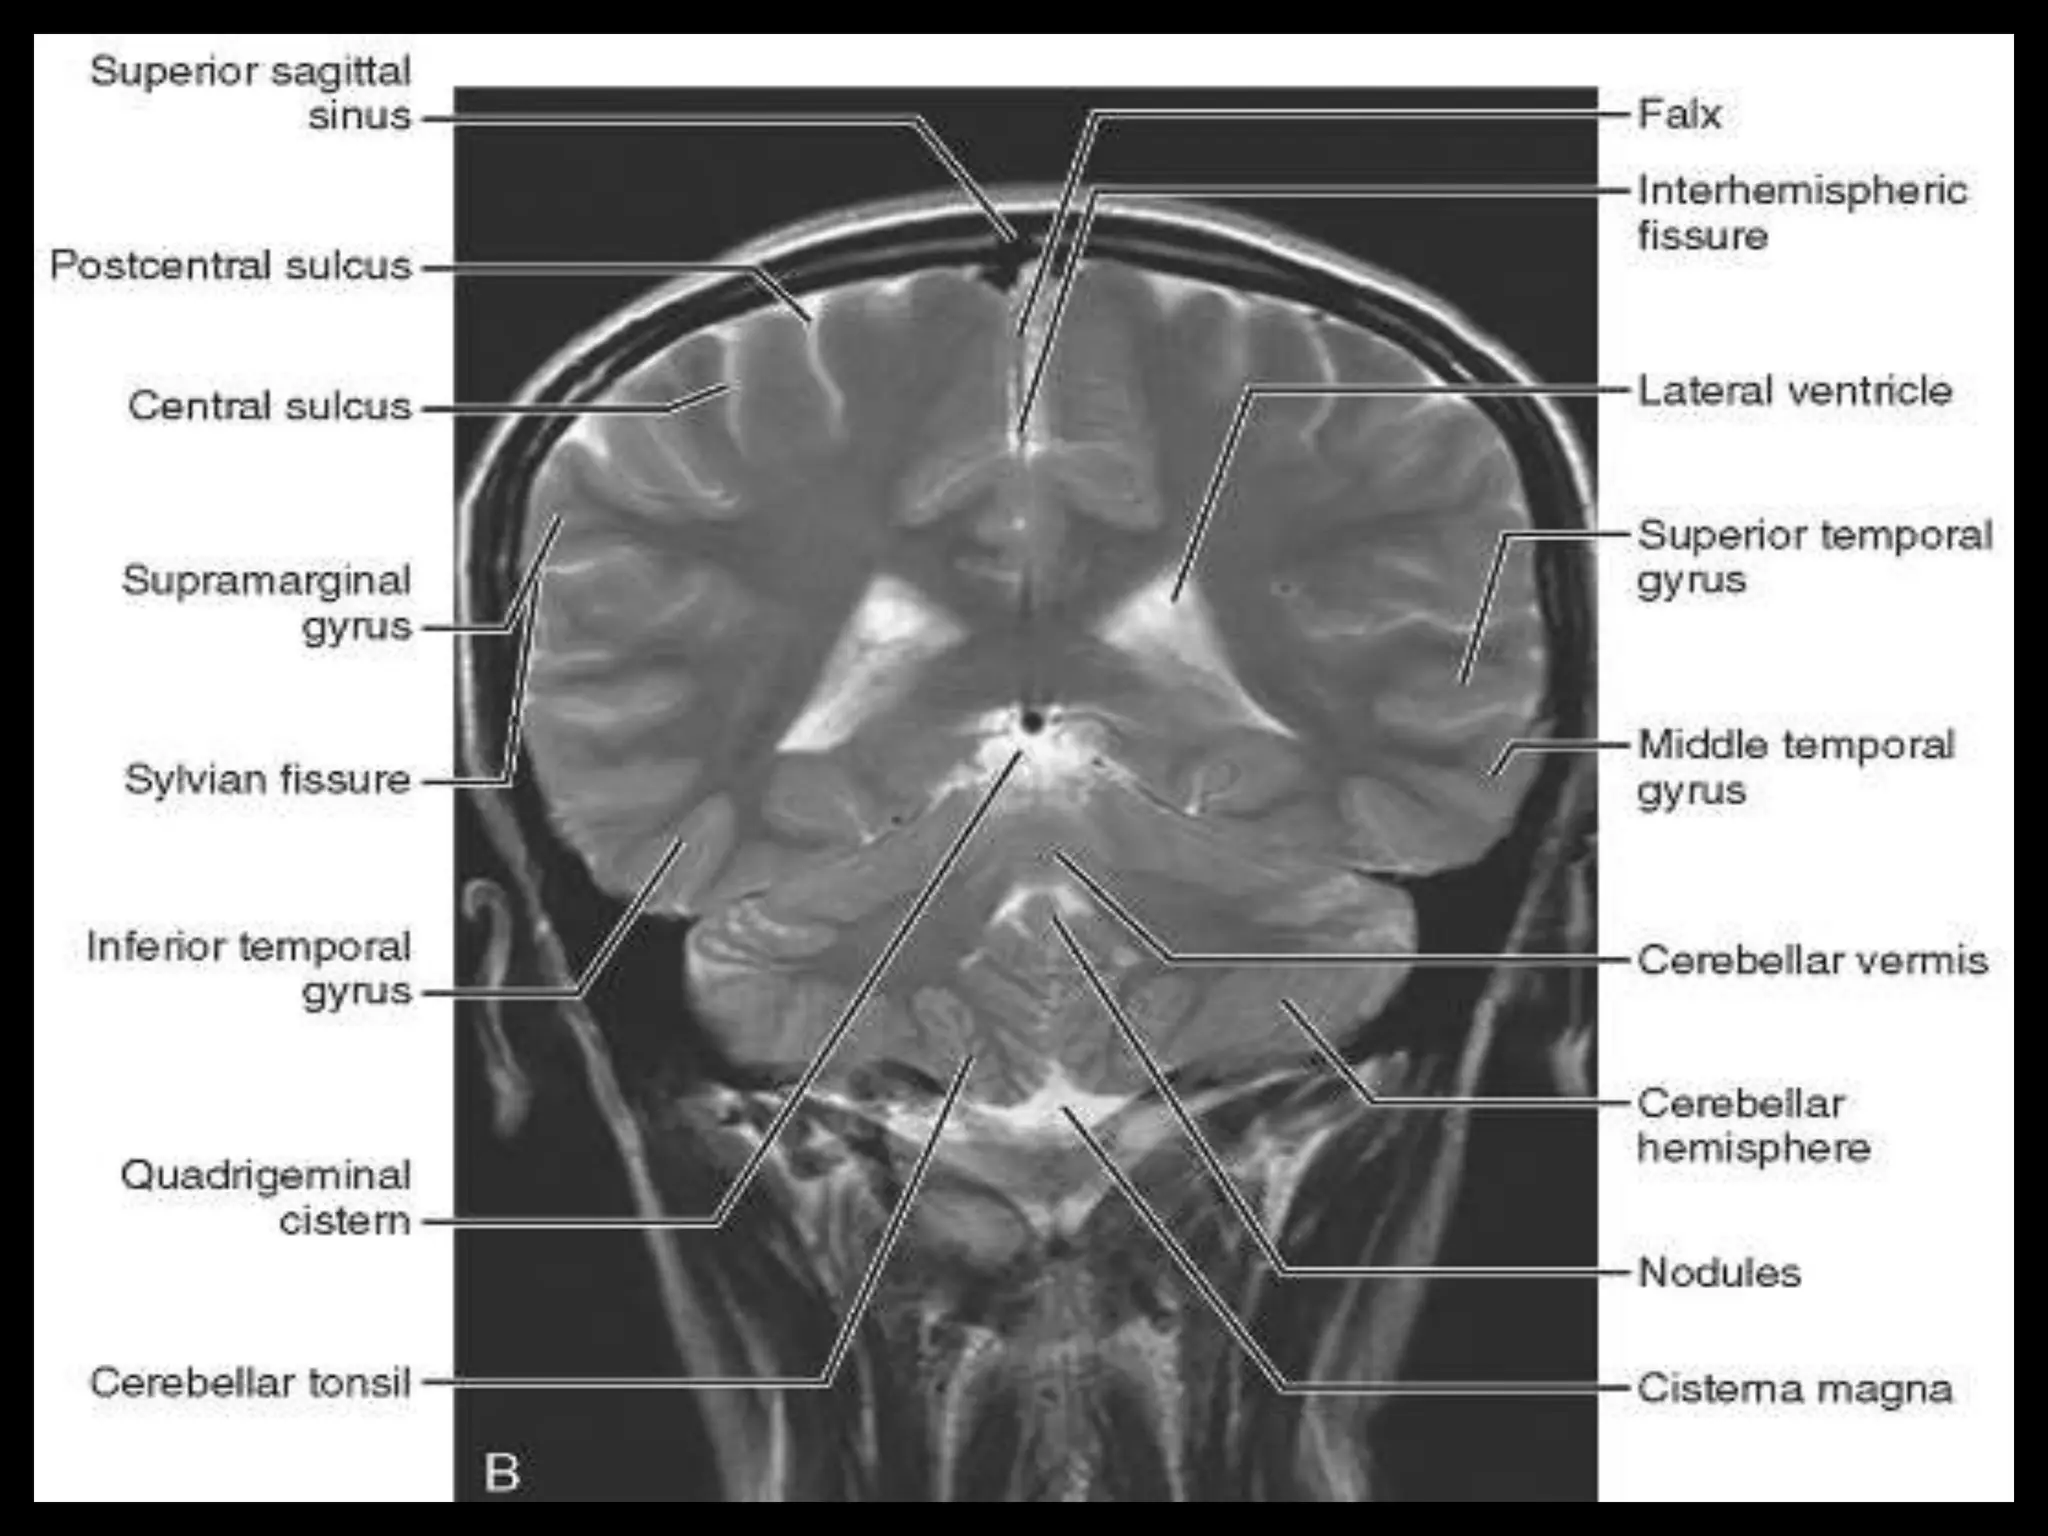

The two cerebralhemispheres are separated by interhemispheric fissures and falx cerebri. On the lateral surface of the brain, the sylvian fissure (lateral fissure) and the rolandic fissure (central fissure) separate the cerebral hemisphere into the frontal lobe, temporal lobe, parietal lobe, and a line drawn from the parieto-occipital sulcus onto the preoccipital notch, delineating the boundaries of the parietal and temporal lobes from that of the occipital lobe. The frontal lobe, the largest of all the brain, has four principal gyri: the precentral gyrus and the superior frontal, middle frontal, and inferior frontal gyri. The precentral gyrus, parallel to the central sulcus, together with the anterior bank of the central sulcus, comprises the primary motor area, which is one of the most important cortical areas for movement. Rostral to the precentral sulcus is the premotor area, another important area for movement. The middle frontal gyrus contains Brodmann’s area 8, known as the frontal eye field, which is important for conjugate eye movements. Another important motor area for speech called Broca’s area, is located at the triangular and the opercular parts of the inferior frontal gyrus in the dominant hemisphere.

In the parietallobe, there are a postcentral gyrus, a superior parietal lobule, and an inferior parietal lobule. The postcentral gyrus is a primary somesthetic area involved in general body sensation. In the temporal lobe, the superior, middle, and inferior temporal gyri are separated by the two transverse sulci. The posterior fossa contains the cerebellum and brain stem. The posterior fossa is outlined by the clivus and petrous bones anteroinferiorly, the tentorium cerebelli superiorly, and the occipital bone posteroinferiorly. The cerebellum is located posteriorly in the two thirds of the posterior fossa, separated from the brain stem by the fourth ventricle. The brain stem occupies the anterior third of the posterior fossa, including the midbrain, pons, and medulla oblongata. The brain derives its vascular supply via two carotid and two vertebral arteries. The internal carotid artery bifurcates terminally into the anterior and middle cerebral arteries. The two vertebral arteries unite at the caudal border of the pons to form the basilar artery.

Sectional Anatomy: NormalAxial CT and MRI Anatomy. On CT and MR scans, the brain has been briefly viewed in infratentorial and supratentorial sections, as described below. CT scans are performed with a 15- to 20-degree angulation to the canthomeatal line at 8-mm increments. MRI scans are generally obtained parallel to the AC-PC line in the axial plane with 6-mm slice thickness. Using the sagittal view, the coronal sections are acquired parallel to the brain stem, and the sagittal sections are obtained perpendicular to the axial section. On MRI studies, cranial nerves IX and X can be demonstrated at this level because they emerge from the postolivary sulcus. The posterior aspect of the cerebellar hemispheres is outlined by the inferior portion of the cisterna magna.